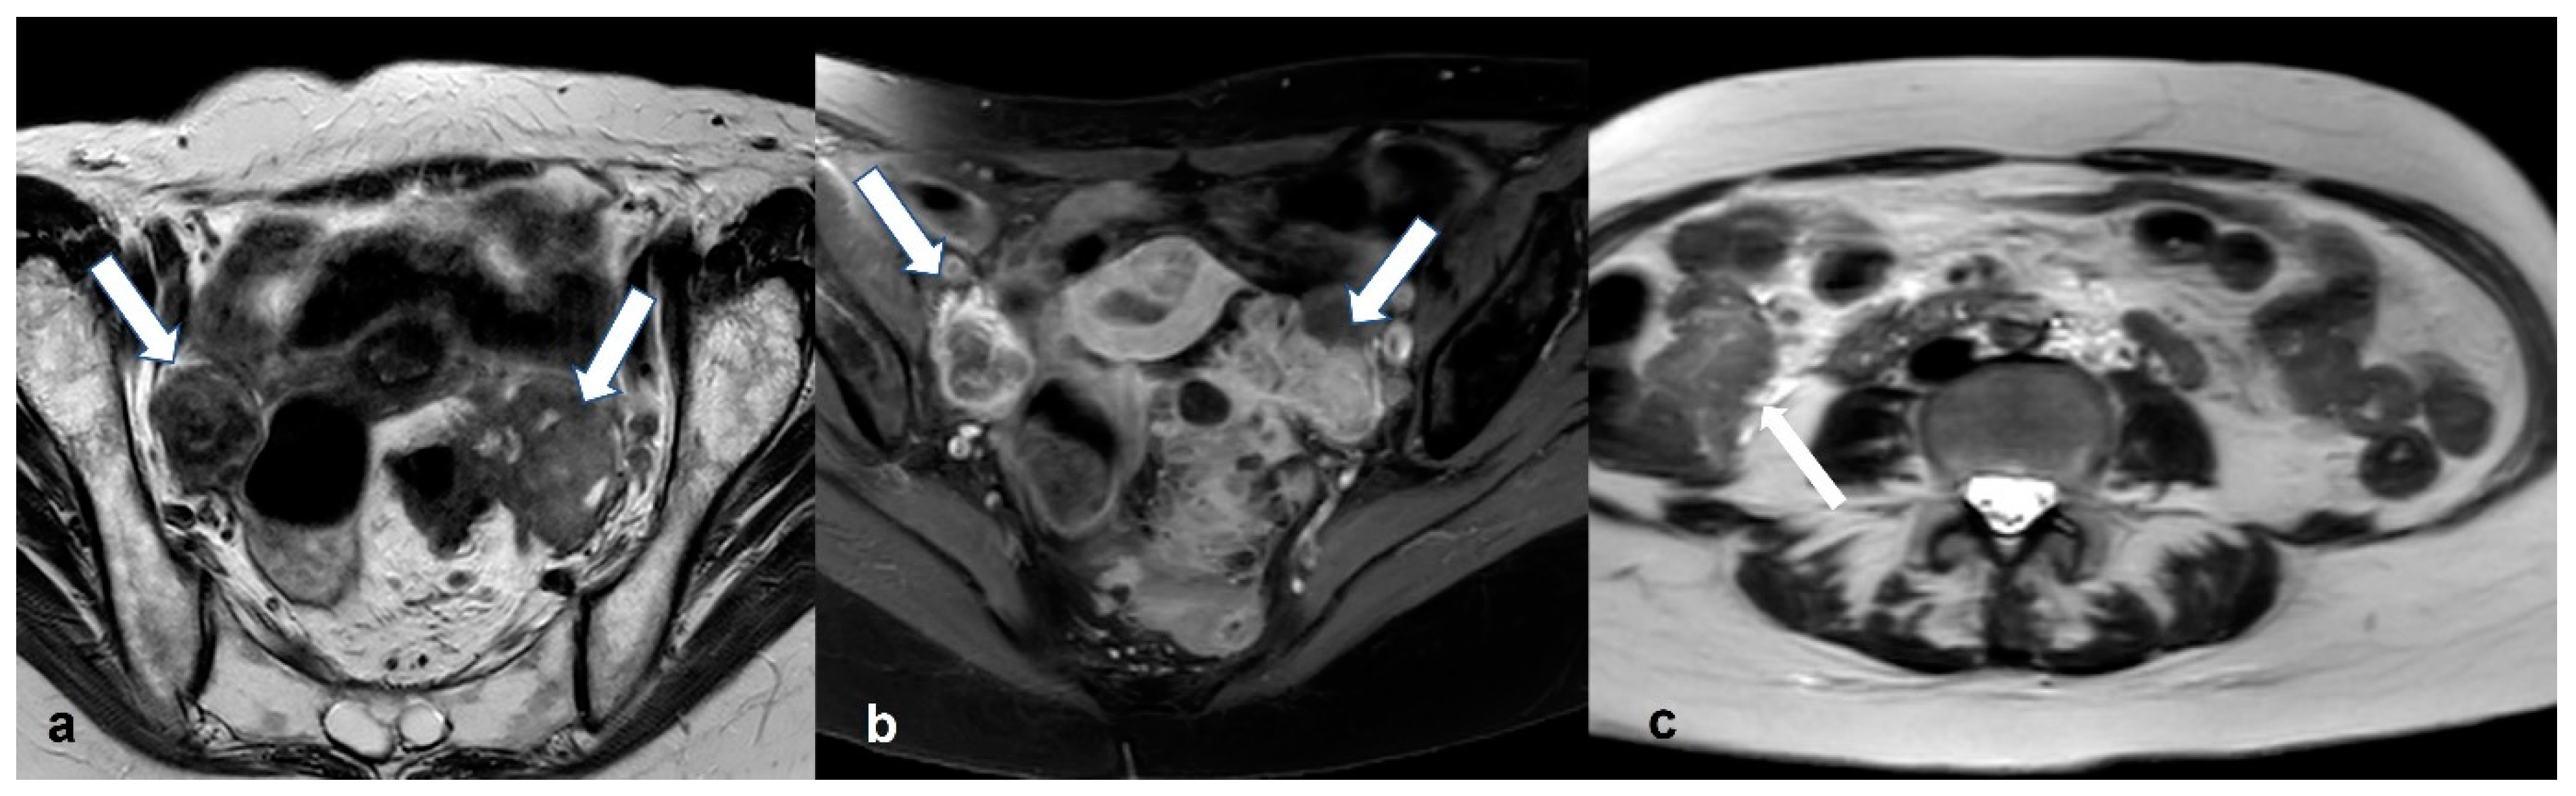

2.1.1. High-Grade Serous Cystadenocarcinoma (HGSC)

2.2.3. Pelvic Inflammatory Disease—Tubo-Ovarian Abscess (TOA)